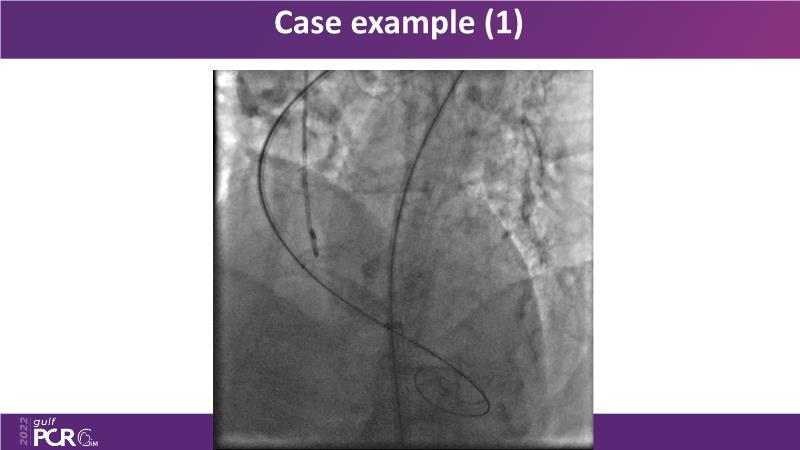

Through the 3 cases presented in this GulfPCR-GIM 2022 session and the highly informative discussion among your peers, learn how to use TAVI with difficult anatomies such as bicuspid aortic valves by relying on imaging.

- To use imaging in planning TAVI with the following clinical scenarios: bicuspid and low coronary height/small annulus